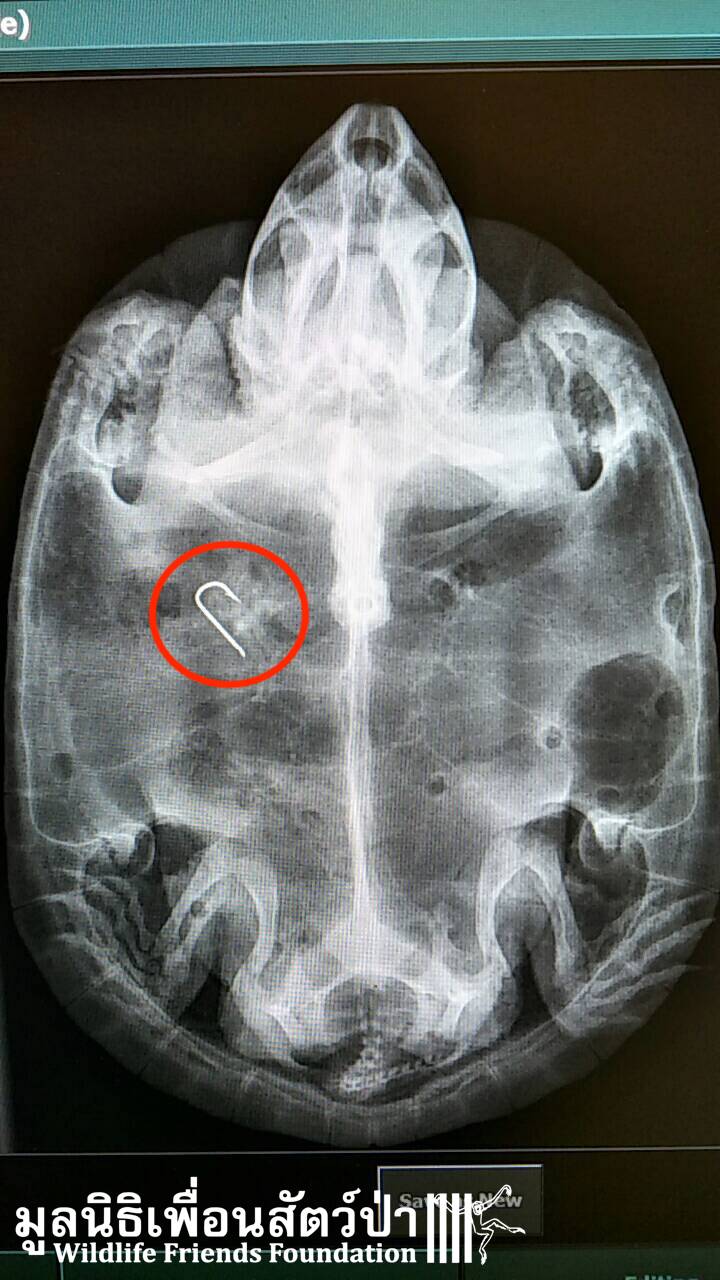

This snail eating turtle was in need of urgent care and is now recovering at our wildlife hospital.

Last week we rescued numerous turtles from a temple in Rayong, see the rescue story here https://bit.ly/2nFimsp. They had been dumped at the temple over a period of years, sadly their living conditions were terrible, with green stagnant water, nothing to hide under and a diet of boiled rice. These poor little critters were dying due to bad diet and bad hygiene. We had to build a new special area to provide the suitable care to these animals, heat lamps and swimming pools have been installed in their new sandy enclosures. The WFFT Vet Team have been performing full health checks on all the turtles, including x-ray. We found fishing hooks inside 3 of the turtles, sadly one did not make it. For now, the other 63 turtles are doing well and enjoying their new clean home with clean water and fresh food. Once they have gone through a quarantine period they will be returned back to the wild. We will keep you posted.